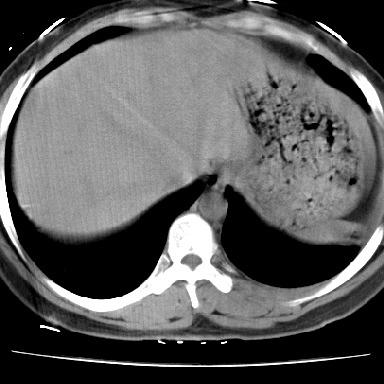

右肺多发小结节影,边界清楚,符合转移瘤的特点;2、左下肺偏心性空洞影,右侧乳腺内高密度影,需要查体除外右侧乳腺肿瘤;3、腋窝淋巴结肿大,考虑转移。

支持癌性空洞:壁厚,无液平,内壁不规则,外壁呈分叶状,较大,偏心性,壁结节,胸膜凹陷,转移灶。

左下肺有空洞,壁厚薄不均,壁结节,两肺多发小结节影,腋窝下可疑淋巴结肿大,综上所述考虑周围性肺癌并两肺转移可能性大,建议穿刺活检。